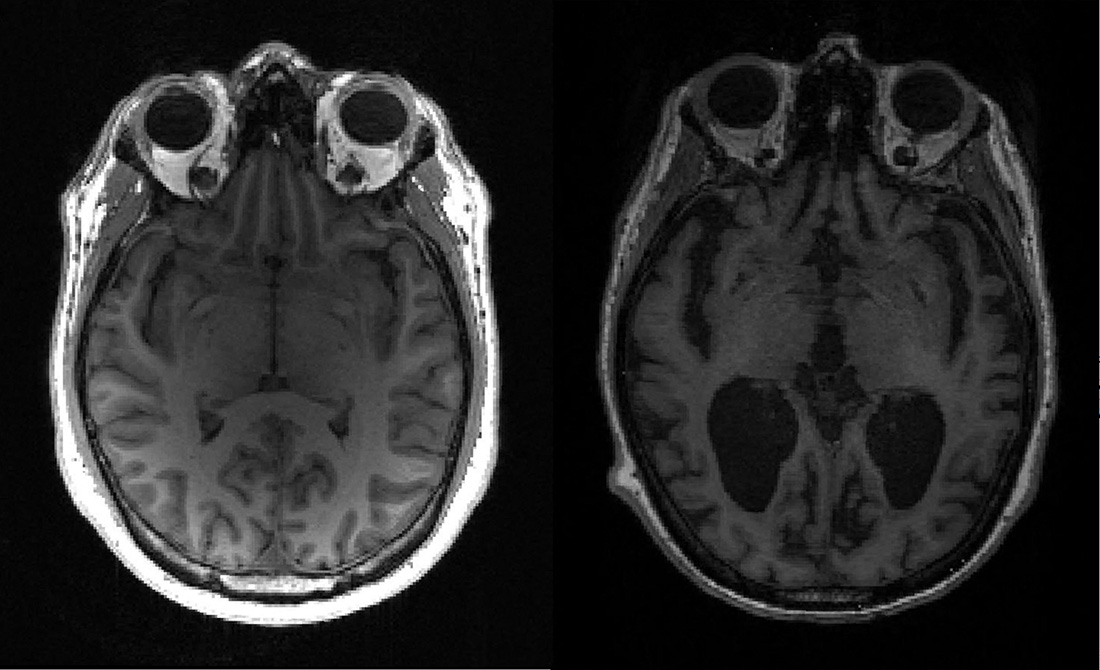

Le Leqembi fait partie d'une nouvelle génération de traitements ciblant une protéine appelée bêta-amyloïde, qui forme des plaques dans le cerveau de patients malades.

Il est toutefois accompagné d'un avertissement: il peut entraîner des effets secondaires graves, comme des oedèmes ou hémorragies cérébrales, qui peuvent être fatals.